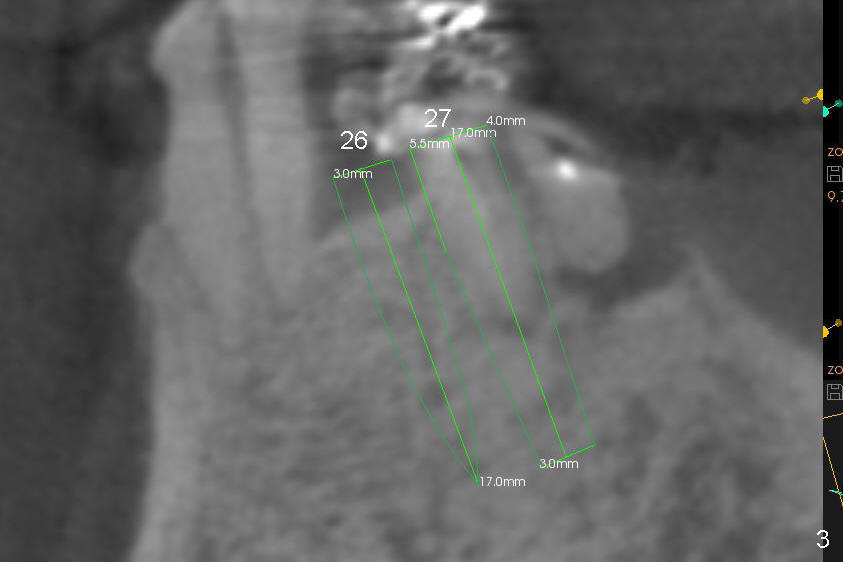

A 85-year-old man has poor dentition (Fig.9). Multiple implants are to be placed at one or two stages (#26-30). If primary stability is obtained for individual implants, they are splinted and immediate provisional is fabricated.

Fig.1-3 are CBCT sagittal sections of the lower right quadrant, whereas Fig.4-8 are coronal sections. The lower left quadrant has been restored.